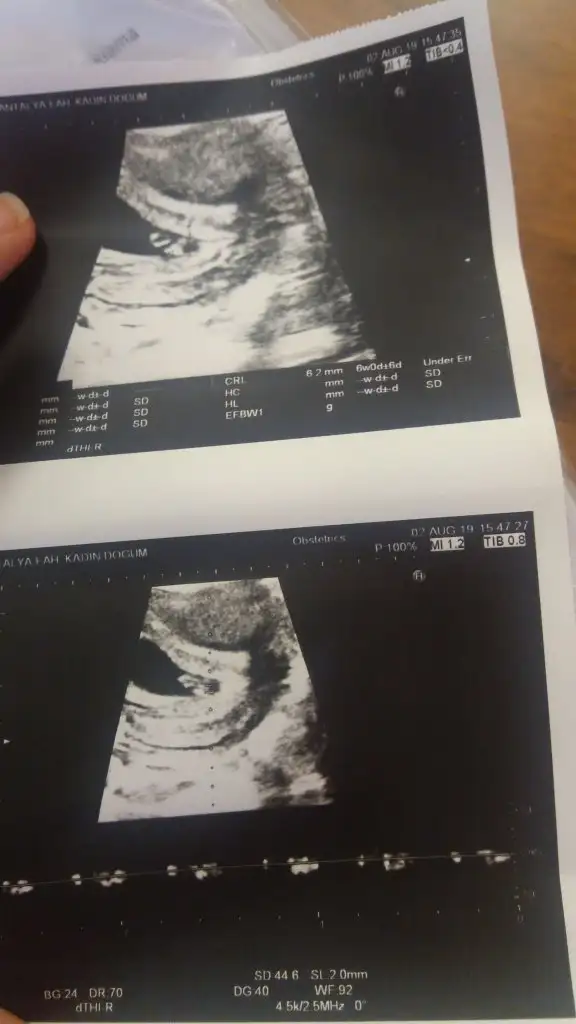

Bu 9 haftalık 6 haftalık halinde nokta var sadece ve solda görünüyorKaç haftalık 6 yada 7 haftalık varsa atarsan daha iyi yorumlanabilir

Soldaysa erkek ama bu teori pek tutmuyor 12. Haftalarda at tekrar canım usg erkek gibi geldi banaBu 9 haftalık 6 haftalık halinde nokta var sadece ve solda görünüyor

6 hafta olmalı buna göre kız varsa 6 hafta paylaşın kese konumu tutmayabilir 11 yada 12 hafta usg paylaşın7 hafta 5 günlük